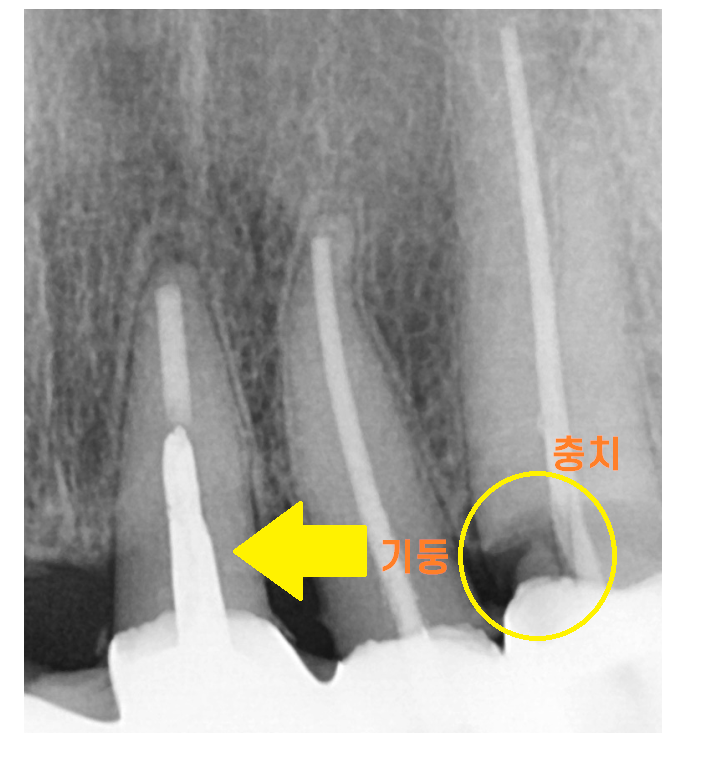

240315

신경치료가 안되어 있는 치아라면

보철부터 벗겨서 상태를 평가하는 것이 우선이지만

치아가 별로 안남을 때 치료하는 기둥이 박힌 치아가 2개

뿌리쪽 충치가 심한 치아 1개

치아가 거의 남아있지 않게 생겼습니다.